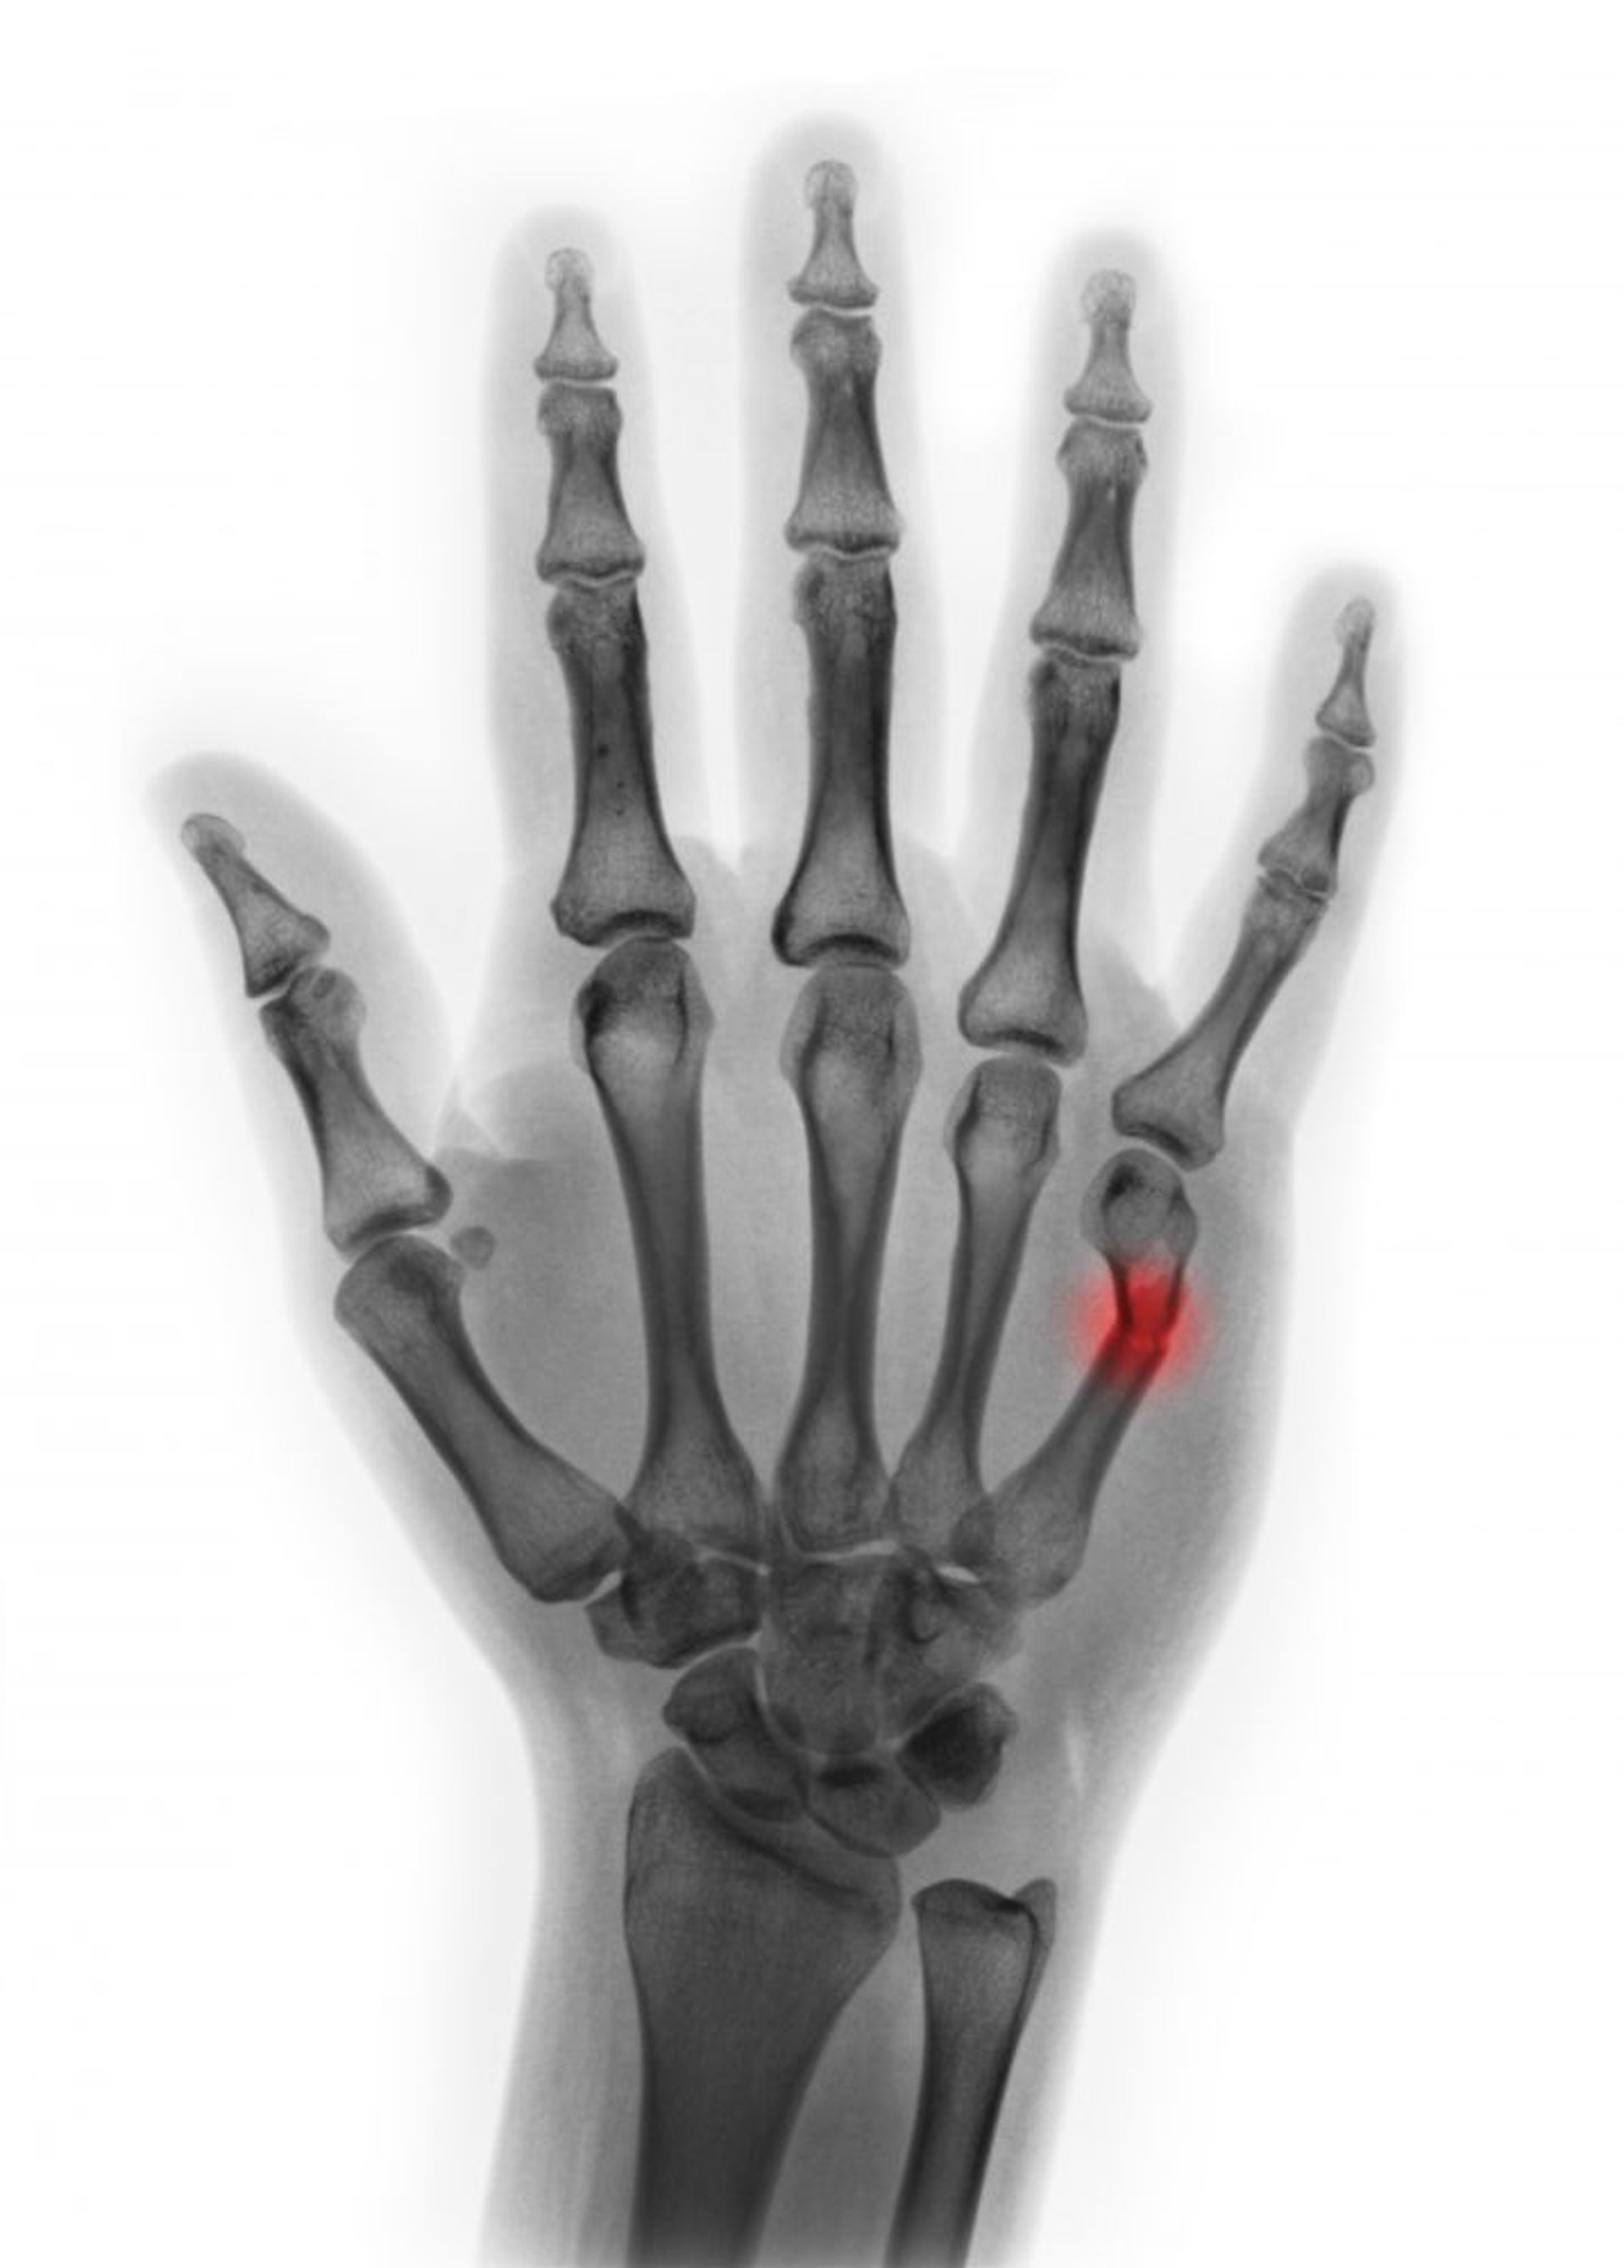

第5中手骨頸部骨折

この着色したX線像には,第5中手骨頸部の骨折が写っている。この画像では,屈曲は45°未満とみられ,整復の必要がないことが示唆される。